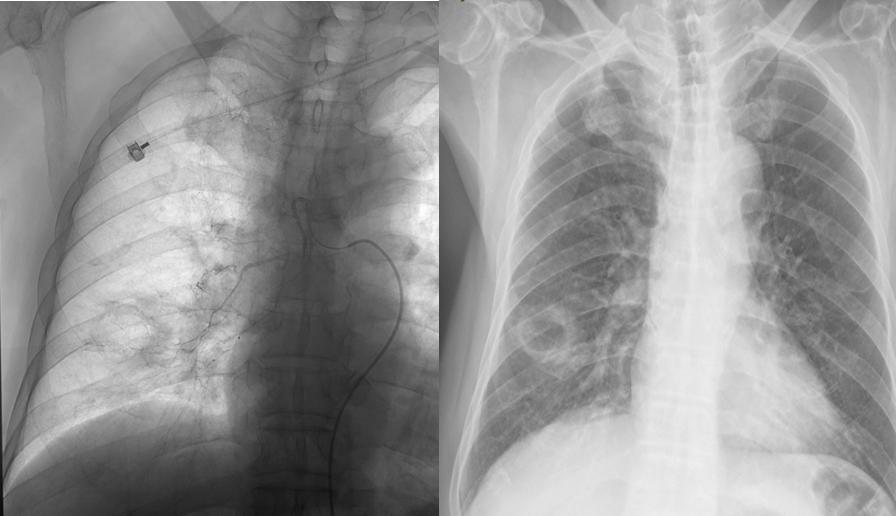

术后影像学检查

术后实验室检查